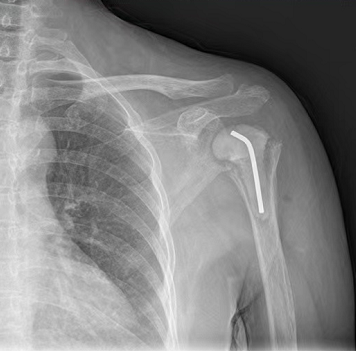

稿件来源:海角社区 发布时间:2021-02-05 15:35:00近日,深圳国家感染性疾病临床医学研究中心/海角社区 (南方科技大学第二附属医院)骨一科成功为一名55岁的骨结核患者置换了肩关节,该手术是一台反置式肩关节置换术,因为难度大,许多医院都没有开展,这也是深圳首台骨结核患者的反置式肩关节置换术。

除了破坏关节以外,骨结核给康女士还带来了严重的肩袖损伤,但传统的肩关节假体是根据人体解剖结构设计的,想取得比较理想的效果往往需要患者的肩袖功能完整。“像抬手这个动作,主要就是依靠肩袖功能实现,如果肩袖损伤,即使做了传统的肩关节置换术也很难再抬起手来,”姜文学说,“只有反置式肩关节置换术能挽救一部分功能。”

反置式肩关节假体的许多细节与人体解剖结构相反,旋转中心向内向下偏移,这一设计延长了三角肌、抬高了力臂、增加了力矩,能最大限度地发挥三角肌的功能代偿患者肩袖功能的不全。

1月28日康女士的手术中,姜文学需要考虑到所有的细节:如果旋转中心太靠上,活动中假体就会容易撞到肩胛骨;肩胛骨本就是松质骨,加之康女士长期疼痛活动受限,她的左肩骨质疏松,骨钉必须打到肩胛骨最结实的地方,否则不一定能钉住;肩胛骨是薄薄一片“趴”在肩上的,如果安装太深或者方向有一点偏差,可能骨钉会顶到胸腔甚至肺部。

在姜文学团队两个半小时的努力下,康女士的手术最终顺利完成,目前她的手已经能抬高70-80度,可以完成洗头、梳头一类的动作,近期即将出院。姜文学介绍,出院后康女士大约需要进行2-3个月的康复训练。